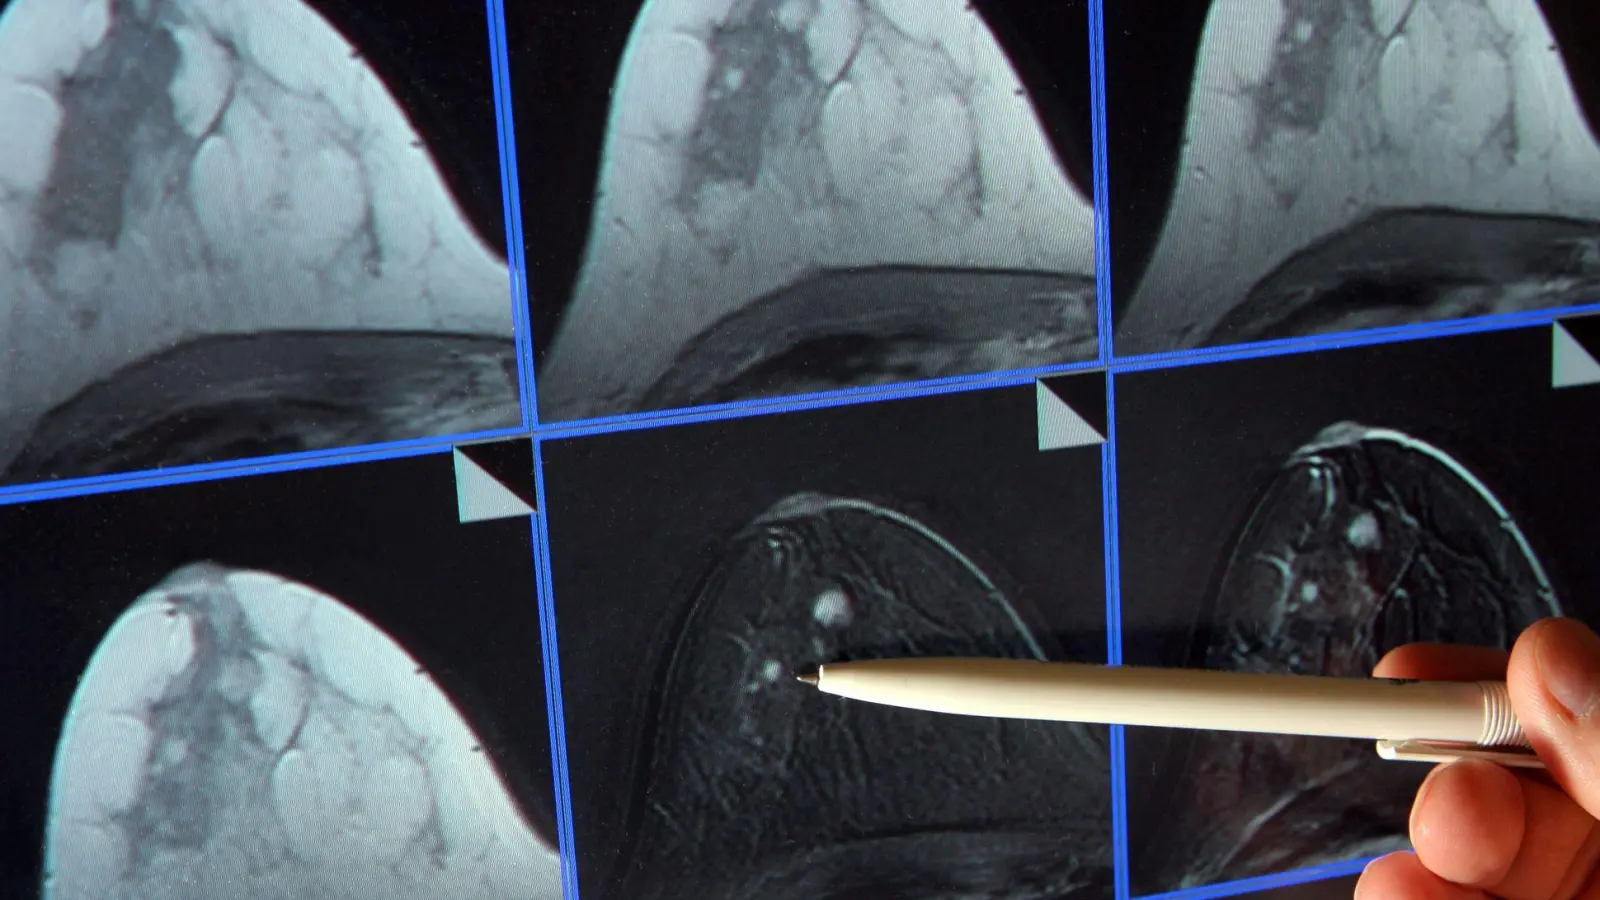

Im Zuge des Mammographie-Screening-Programms können Frauen alle zwei Jahre eine Röntgen-Untersuchung der Brust zur Früherkennung in Anspruch nehmen. (Archivbild) (Foto: Jan-Peter Kasper/dpa-Zentralbild/dpa)